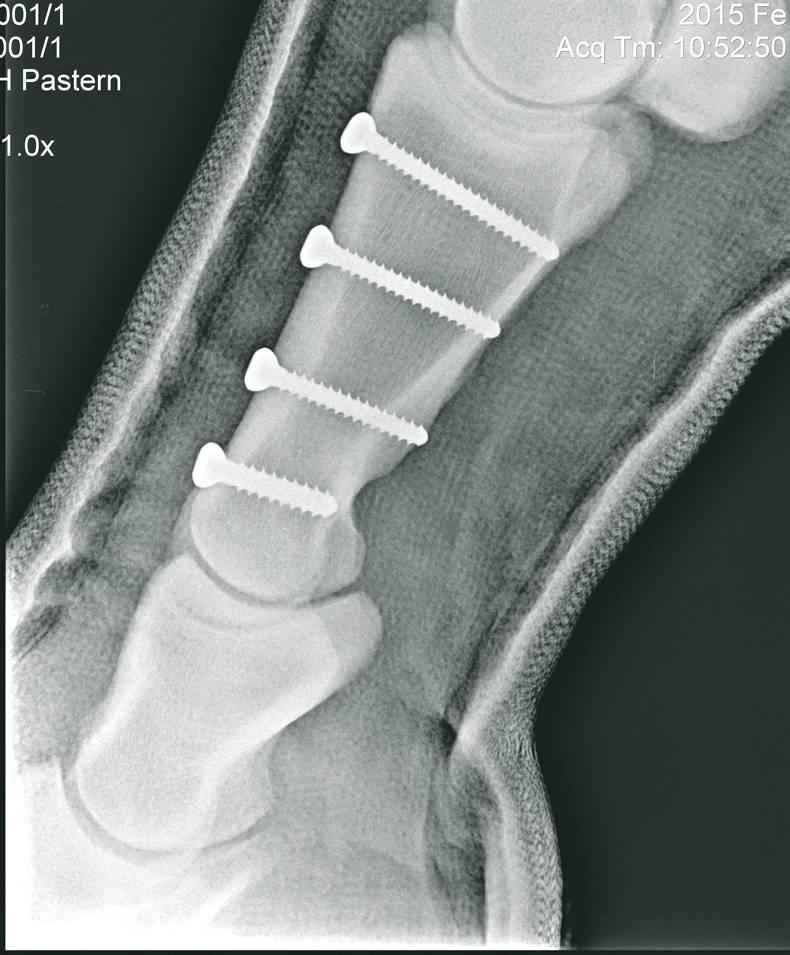

FRACTURES of the long pastern bone, one of the bones forming the fetlock joint, are among the most common fractures affecting the racehorse.

Fractures in the pastern are most commonly sagittal fractures where the bone fractures straight down the centre. Described colloquially as a ‘split pastern’, such fractures typically range from incomplete non-displaced fractures, where the fracture line extends from the fetlock joint downwards into the pastern bone, to complete displaced fractures which extend the whole way through the bone from the fetlock joint into the pastern joint.